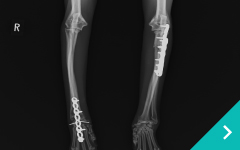

関節鏡を用いた関節内精査と低侵襲手術、関節外法やTPLO法による膝関節再建、MPLG4に対する矯正骨切りを用いた整復、LCPを用いた骨折整復など難易度の高い手術にも対応しております。

犬猫の骨折

犬猫の

骨折